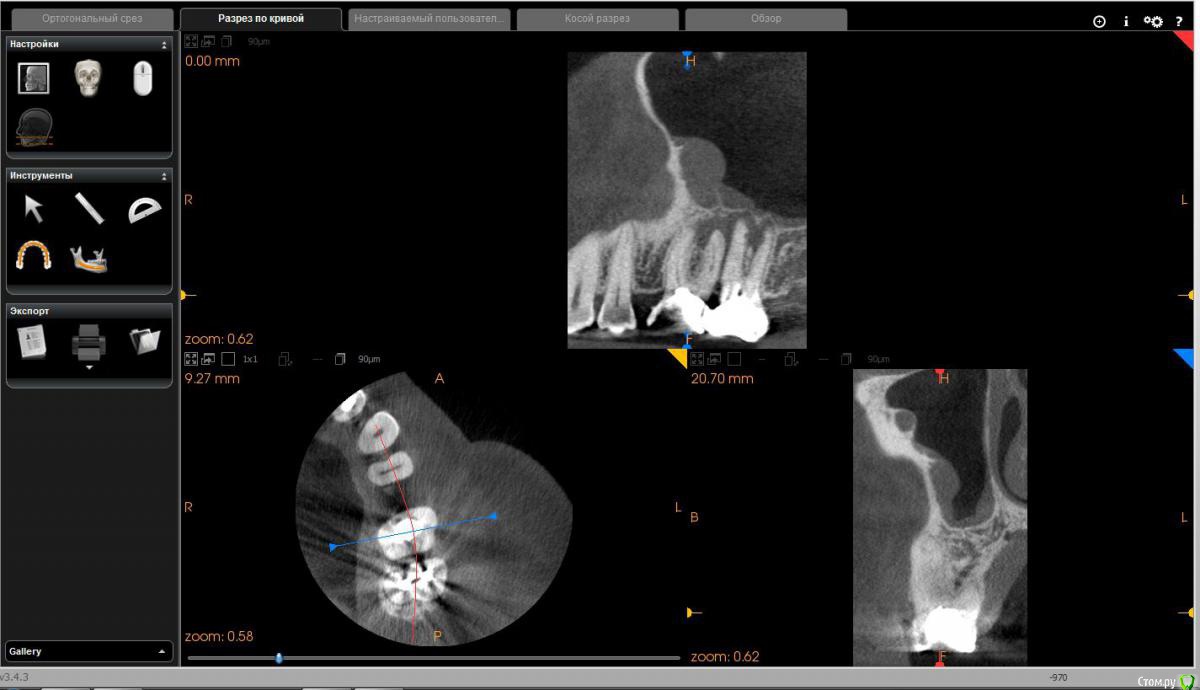

Диана135 Опубликовано 31 марта, 2017 Поделиться Опубликовано 31 марта, 2017 Здравствуйте! Год назад лечила зубы, осенью над одним из них появился флюс, который до сих пор не исчезает, это доставляет мне дискомфорт. Стоит ли продолжать лечение или проще удалить? Прилагаю описание КЛКТ: Зуб 2.6 коронковая часть восстановлена рентгеноконтрастным материалом. Трех корневой, четырёх канальный (в медиально-щечном 2 канала). В медиально-щечном корне каналы прослеживаются, в одном из каналов, в верхней трети определяются фрагменты рентгеноконтрастного материала. В небном корне в верхней трети рентгеноконтрастный материал. В средней трети корня определяется внутрикорневой очаг деструкции 2,2×3,7 мм с резорбцией дистального края и линией просветления от очага деструкции в медиальную сторону апикальной трети. В проекции медиально- и дистально-щечных корней определяется ограниченный очаг деструкции однородной структуры, с неровными контурами, с разрушением наружной кортикальной пластинки и распространением процесса в сторону корней 2.8 зуба. Кортикальная пластинка дна верхнечелюстного синуса в проекции деструкции истончена с набуханием слизистой до 4 мм.Зуб 2.7 Коронковая часть восстановлена рентгеноконтрастным материалом. Трех корневой, четырёх канальный (в медиально-щечном 2 канала). В каналах определяется рентгеноконтрастный пломбировочный материал: в медиально-щечном корне, один из каналов не обтурирован, другой не до верхушки, в дистально-щечном обтурация не до верхушки, в небном до апикального отверстия. В области верхушек медиально и дистально щечных корней определяется деструкция до средней трети длины корней, с расширением пространства периодонтальной связки.Отмечается общая горизонтальная убыль костной ткани до 3 мм. Ссылка на комментарий

Диана135 Опубликовано 1 апреля, 2017 Автор Поделиться Опубликовано 1 апреля, 2017 Скриншоты снимка. Ссылка на комментарий